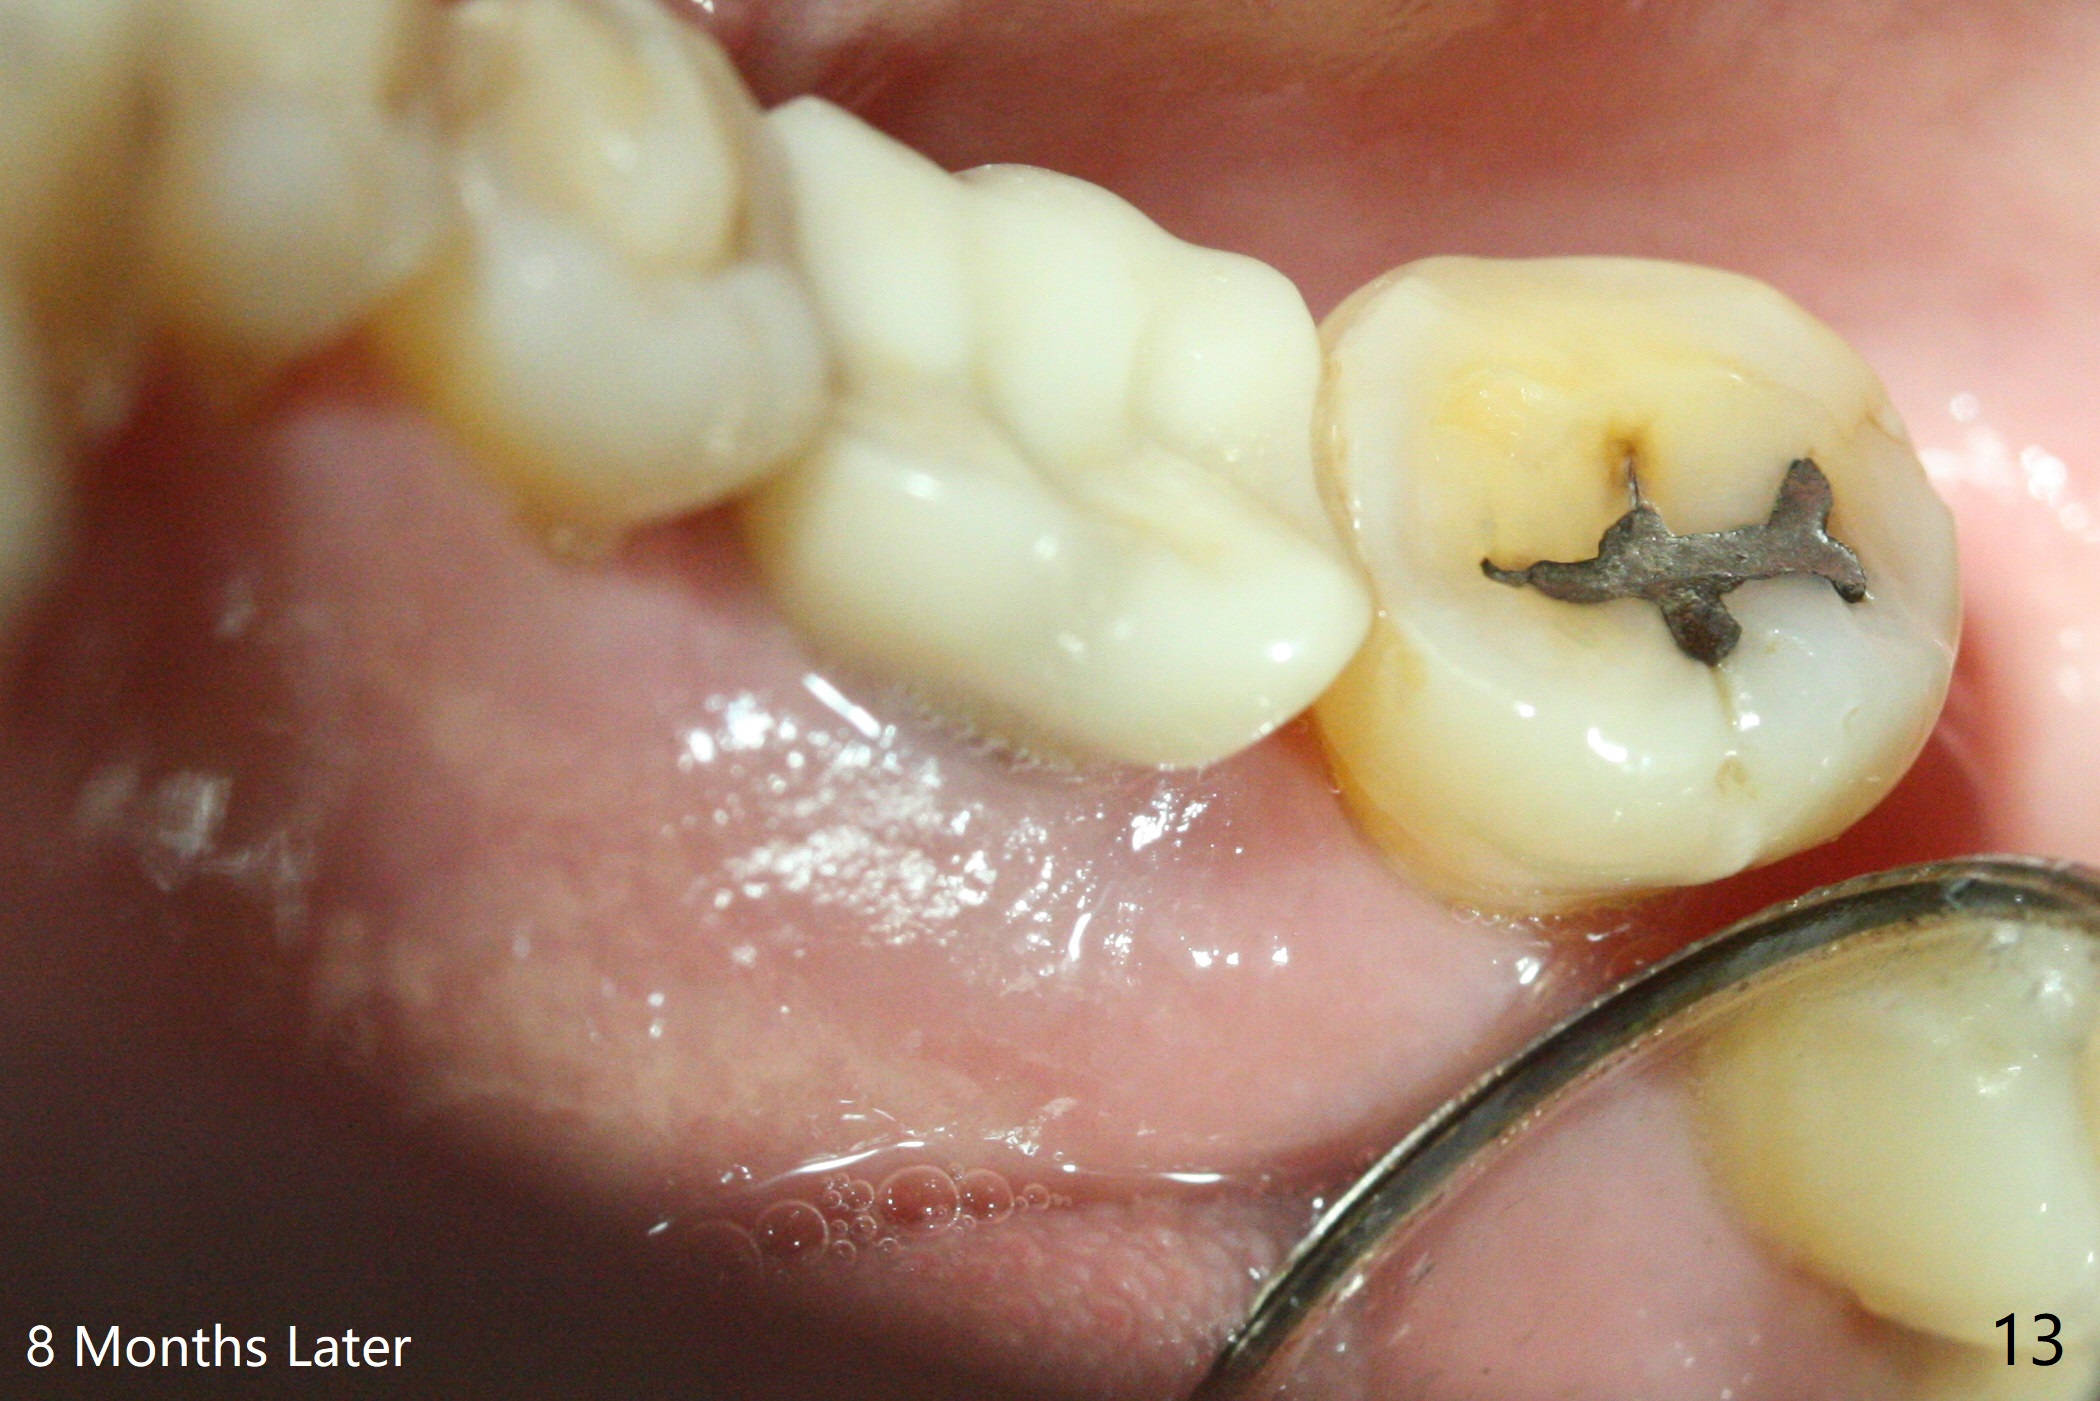

There is no symptom or sign of periimplantitis 3 years 8 months post 2nd bone graft (Fig.7-10). However, the patient complains of gingival hemorrhage 8 months later (Fig.11,12 (buccal), 13 (lingual view)). Water Pik is recommended.